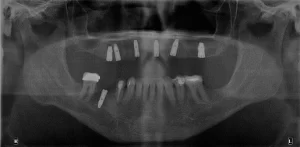

Se decide colocar implantes de zirconio, rehabilitación dental final con coronas de zirconio.

se realiza planeación quirúrgica computarizada, confección de guía de fresado y de provisionales acrílicos.